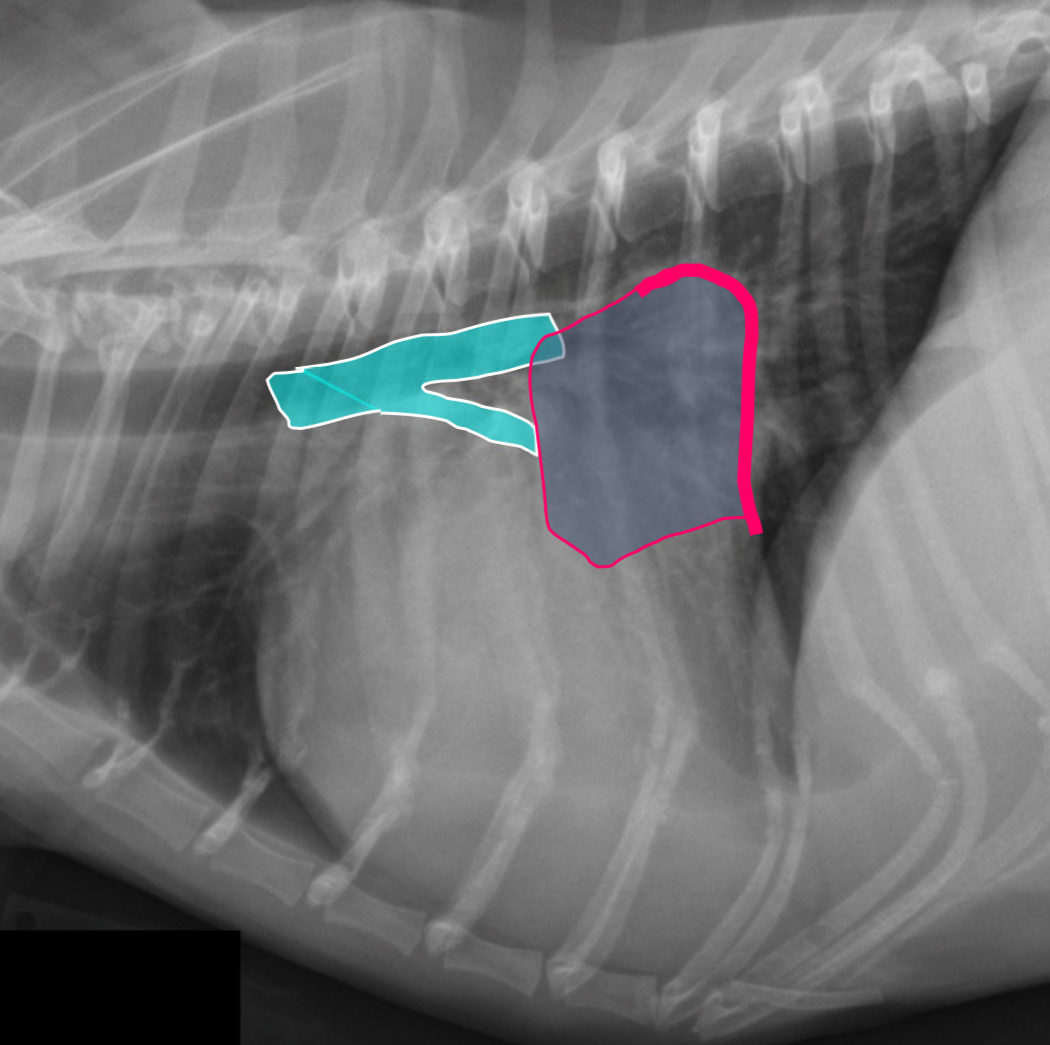

What part of the heart is enlarged

LAE

3 features of LAE on DV

-double opacity sign

-separation of main stem bronchi

-LA bulge at 2:30-3 o’clock